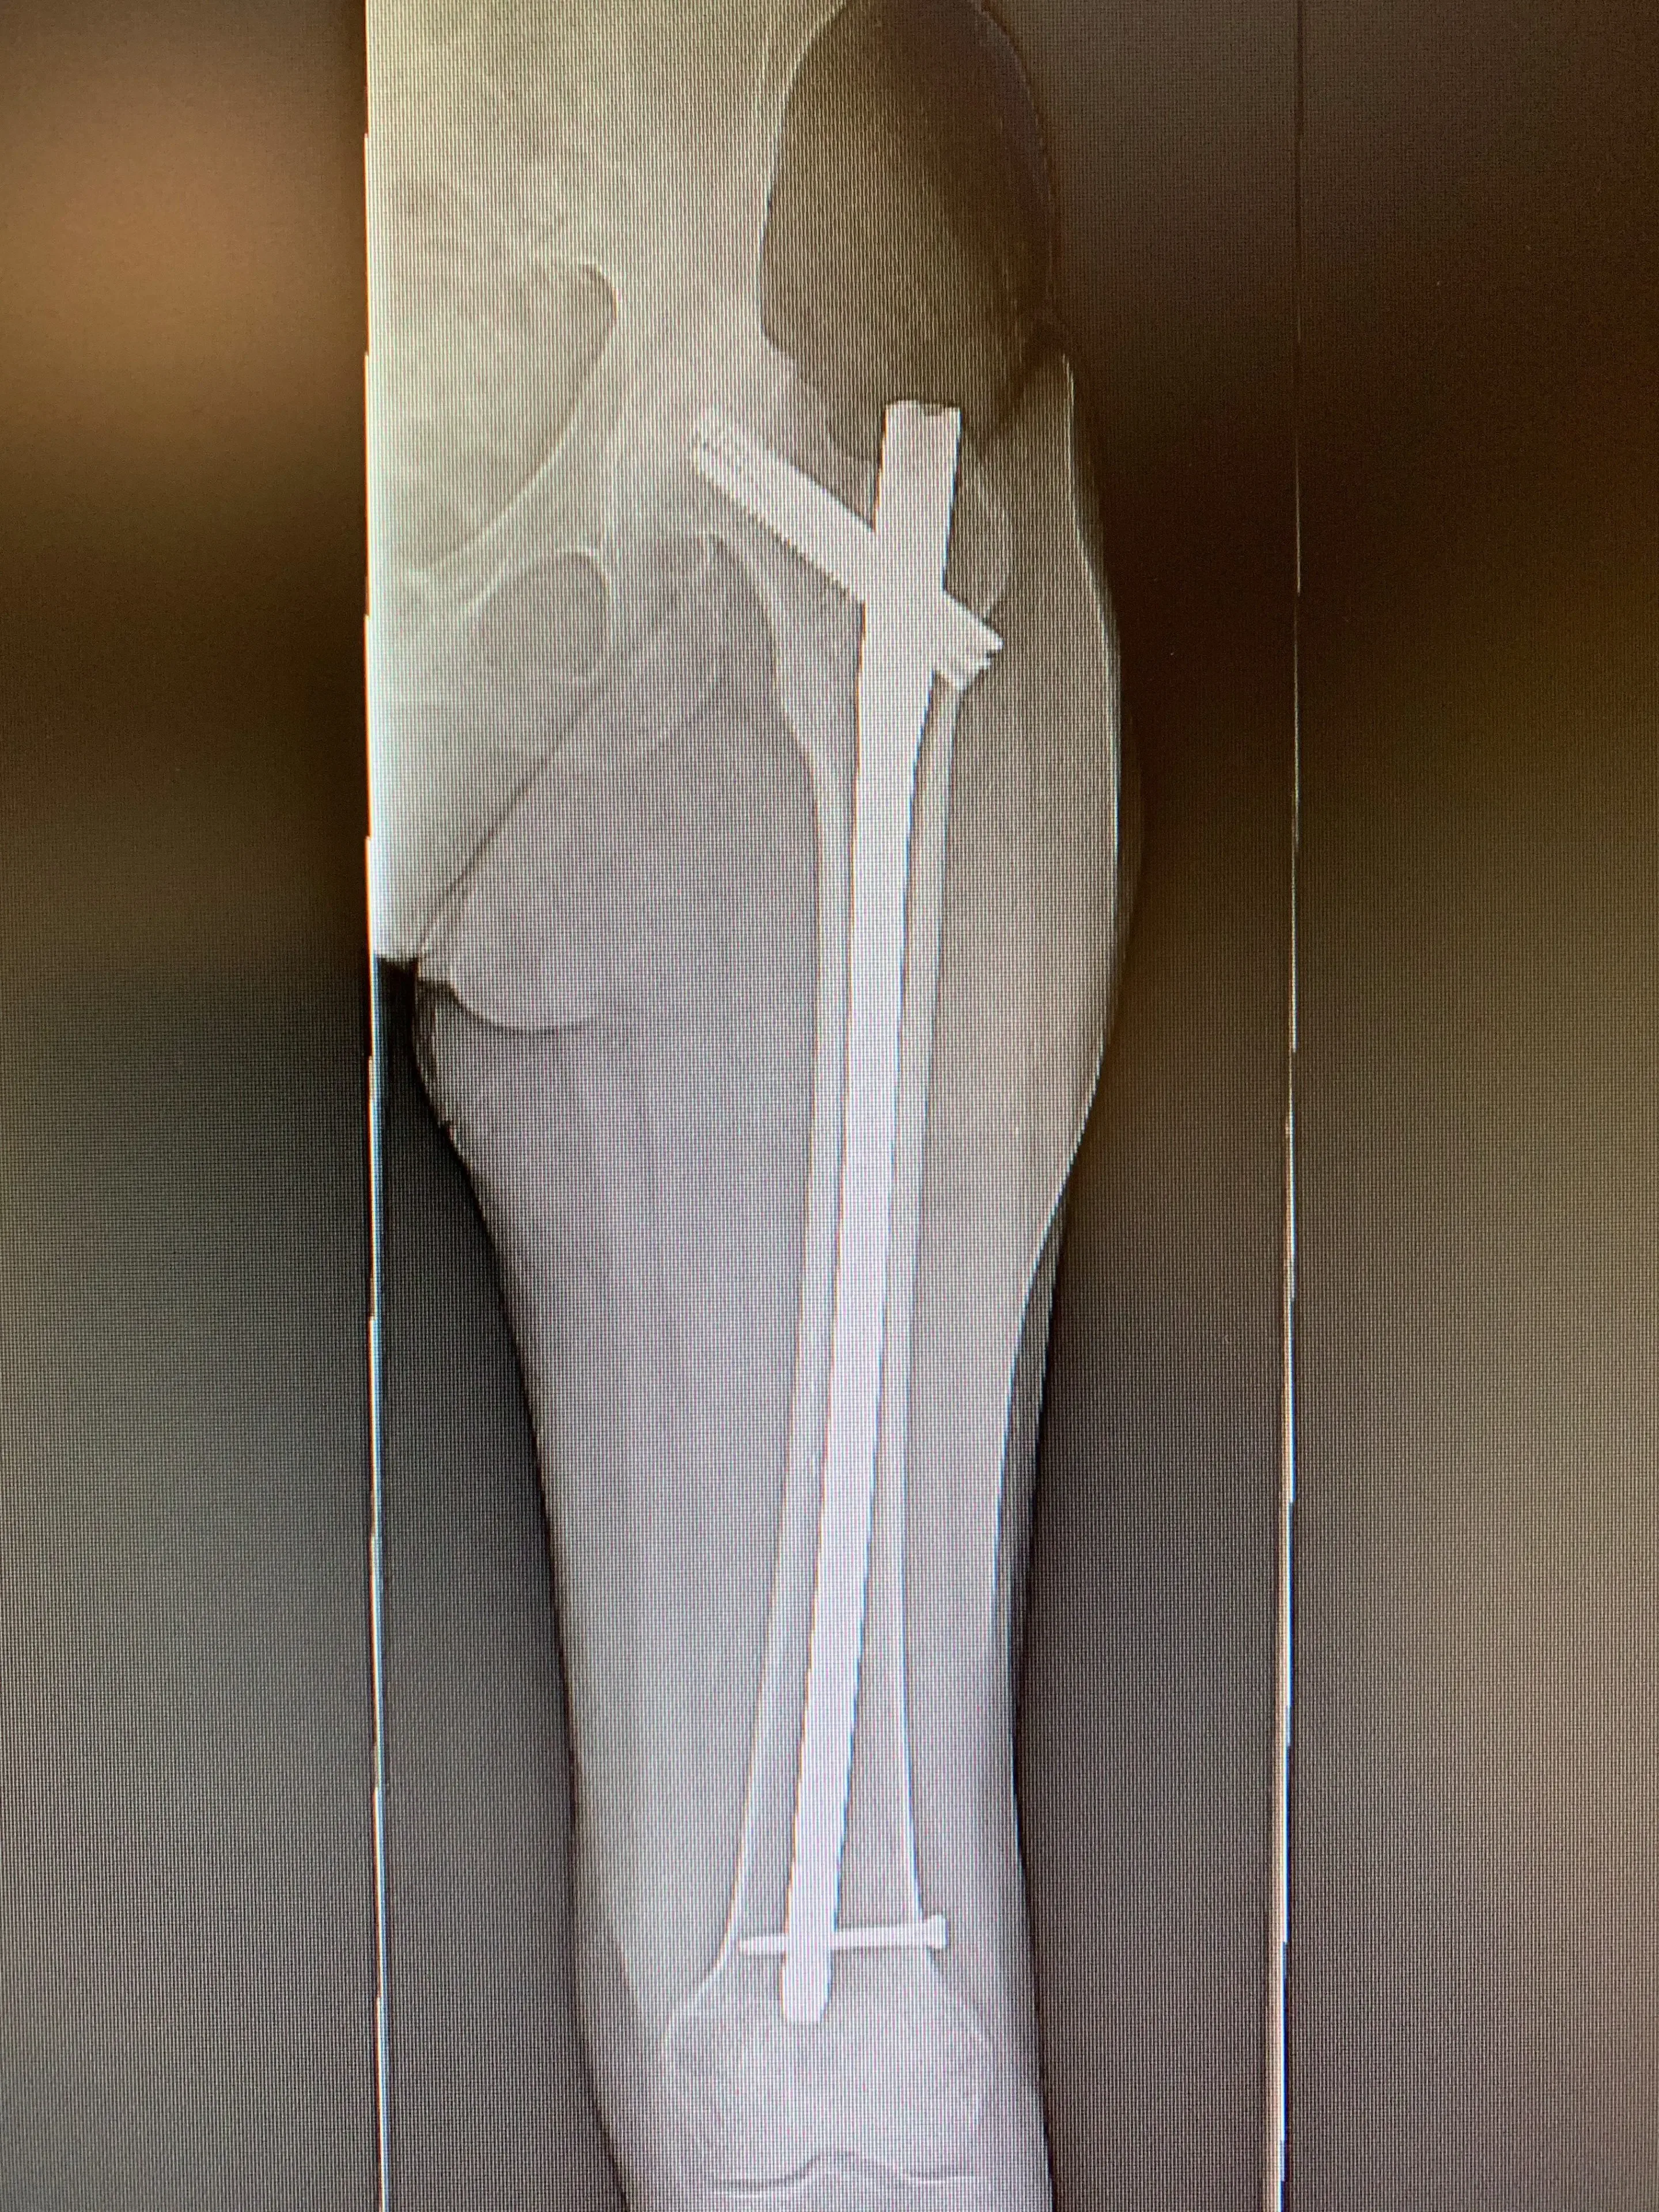

Her X-rays revealed her previous surgical hardware and a healed femur fracture with a small malunion in her femoral canal. Her hip was severely arthritic, with almost no joint space visible at all.

Pre-op